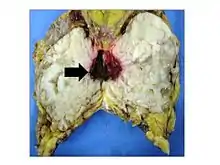

Phyllodes tumors (from Greek: phullon leaf), also cystosarcoma phyllodes, cystosarcoma phylloides and phylloides tumor, are typically large, fast-growing masses that form from the periductal stromal cells of the breast. They account for less than 1% of all breast neoplasms.

This is predominantly a tumor of adult women, with very few examples reported in adolescents. Patients typically present with a firm, palpable mass. These tumors are very fast-growing, and can increase in size in just a few weeks. Occurrence is most common between the ages of 40 and 50, prior to menopause. This is about 15 years older than the typical age of patients with fibroadenoma, a condition with which phyllodes tumors may be confused. They have been documented to occur at any age below 12 years.

Phyllodes tumors are a fibroepithelial tumor composed of an epithelial and a cellular stromal component. They may be considered benign, borderline, or malignant depending on histologic features including stromal cellularity, infiltration at the tumor's edge, and mitotic activity.[1] All forms of phyllodes tumors are regarded as having malignant potential. A large series from the M.D. Anderson Cancer Centre reported the incidence of each as benign (58%), borderline (12%), and malignant (30%). Malignant phyllodes tumours behave like sarcomas and can develop blood-borne metastases. Approximately 10% of patients with phyllodes tumours develop distant metastases and this can go up to 20% in patients with histologically malignant tumours.[2] The commonest sites for distant metastases are the lung, bone, and abdominal viscera. Rare sites of metastasis, such as to the parotid region, have also been described.[3]